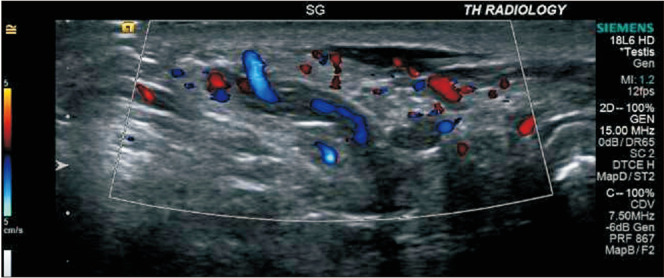

Spontaneous pampiniform venous plexus thrombosis may cause chronic scrotal pain.

自发性阴囊静脉丛血栓可能会导致慢性阴囊疼痛。